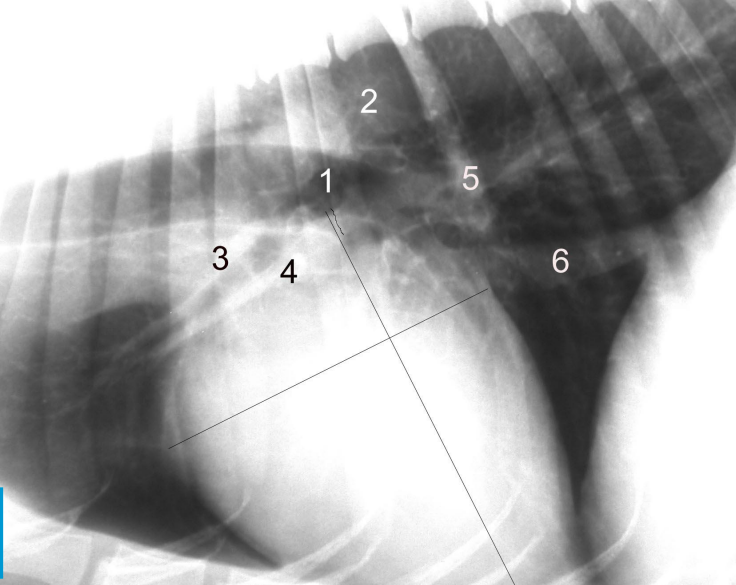

Radiología de tórax

- NO SOLO ECOCARDIO para ver si hay problema pulmonar

- Con una radiologia hay que ver:

- Si hay cardiomegalia

- Signos de congestion

- Hay hipertension pulmonar

- Signos de congestion:

- Arterias y venas pulmonares (Si estan mas grande, hipertension o congesion pasiva)

- Patrones pulmonares → edema pulmonar

- Cardiomegalia

- Signos de congestión:

- Dilatación de arterias y venas pulmonares

- Distensión de vena yugular

Hay radiografias de distintos problemas